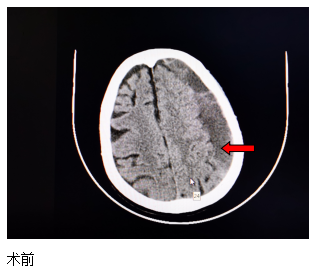

近日,一位84歲高齡患者來江寧中院就診,表現(xiàn)為:右側(cè)肢體的力量下降、不能獨(dú)立站立、言語不利、吐字不清。經(jīng)頭部CT檢查發(fā)現(xiàn),患者左側(cè)大面積慢性硬膜下血腫,嚴(yán)重壓迫腦組織。

患者收入院后,完善各項(xiàng)檢查,無明顯手術(shù)禁忌,中醫(yī)院神經(jīng)外科團(tuán)隊(duì)經(jīng)過精心周全的準(zhǔn)備,為其實(shí)施了腦膜中動脈栓塞結(jié)合硬通道血腫穿刺引流的復(fù)合手術(shù)。術(shù)后第二天,患者肢體無力的癥狀得到了明顯改善,語言表達(dá)也恢復(fù)如初?;颊呒凹覍賹Υ酥委熜Ч浅M意。